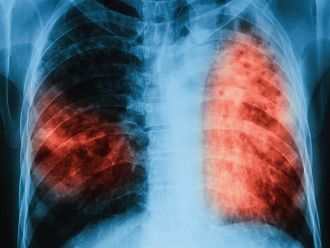

За втори път през 2018 г. ще се проведат безплатни прегледи за туберкулоза в лечебни заведения за диагностика и лечение на туберкулозата във всички областни градове на страната, съобщиха от Министерство на здравеопазването.

По време на „Седмицата на отворените врати“ на всеки желаещ се предлага скрининг за риска от туберкулоза чрез анкета и консултации. На лицата, които са в риск се провеждат допълнителни прегледи и изследвания. При откриването на случаи на туберкулоза своевременно се предприемат мерки за хоспитализация и лечение, в резултат на което се прекъсва веригата за предаване на инфекцията, изтъкват от МЗ.

От там допълват, че по време на проведената през март 2018 г. кампания общо анкетирани за туберкулоза са 3 004 лица. На 1436 лица в риск от туберкулоза са извършени медицински прегледи и допълнителни изследвания. Открити са 32 лица с туберкулоза и 110 лица с латентна туберкулозна инфекция, които са започнали лечение.